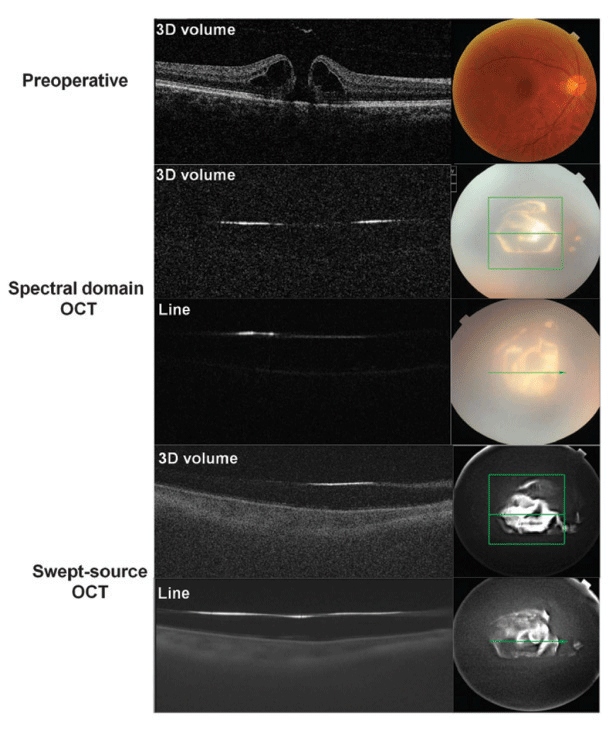

| A readout from the DRI OCT Triton showing spectral domain vs. swept source optical coherence tomography scans, and the device itself (below) showing the operator screen. |

Topcon also notes the DRI OCT Triton can visualize deeper pathology, penetrating the choroid and even the sclera, without being obscured by media opacities or hemorrhage. The DRI OCT Triton can visualize from the vitreous through to the sclera with high sensitivity and speed, the company says. The instantaneous capture of a high-density data cube, composed of 512 B-scans, reduces interpolation between slices, revealing imagery. The instrument also features wide-field OCT scanning (12 x 9 mm) with a reference database.

“The most striking advantage of SS-OCT is speed and depth,” Dr. Lavinsky says. “With Triton OCT, we are able to quickly acquire wide-field OCT with high-quality scans. And we are able to analyze the optic disc, macula and retinal vasculature with just one cube.”

He also notes that, in his experience, the Triton achieves greater depth than other OCT platforms he’s used. “With SS-OCT we are capable of acquiring high-resolution images of the vitreous down to the sclera with details that we were not able to get previously with other technologies,” Dr. Lavinsky says.